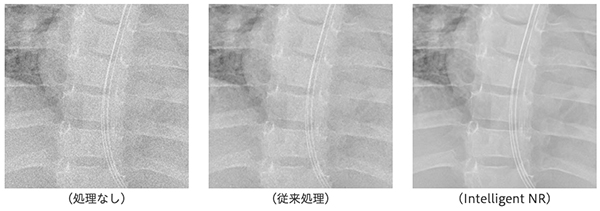

参考:“Intelligent NR”を使用したノイズ低減処理イメージ比較

1.X線撮影装置の性能評価用器具(バーガーファントム)撮影時のノイズ低減イメージ

2.被写体別のノイズ低減イメージ

2-1. 小児胸部撮影時

2-2. 骨盤撮影時